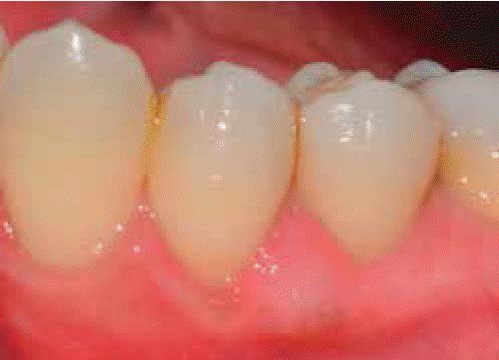

Controls: lesion volume decreased after a week, nevertheless, the area still exhibited a reddish hue, therefore, it was kept under observation (Figure 7). Two weeks later, a slight volume increase with whitish and reddish hue was observed, thus a relapse was suspected. At the third week decrease of tissue volume was observed without any presence of inflammatory signs.

During a seven month follow-up suitable oral hygiene level was observed, no lesion relapse was observed (Figure 8).